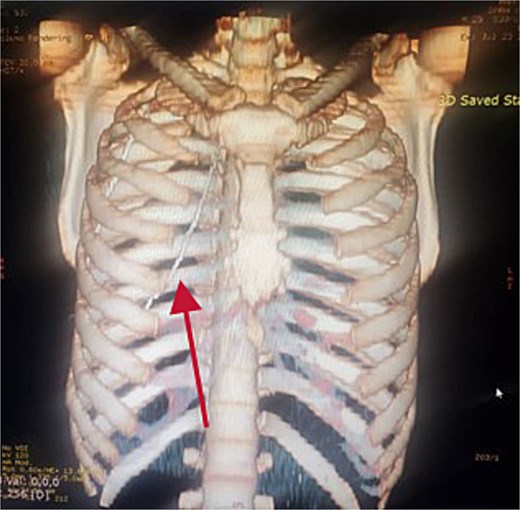

Further evaluation with chest ultrasound and computed tomography (CT) thorax, performed 48 h later, confirmed the guide wire’s position (Figs 3 and 4). The imaging studies demonstrated that the tail end of the guide wire was lodged in the right subclavian vein, while the remainder was situated in the pleural space of the right hemithorax. Notably, the guide wire was in contact with the 7th rib along the anterior and mid-axillary line. Additionally, a moderate right hemothorax had developed.

The patient was resuscitated and prepared for surgery via a 16G peripheral line. A mini-thoracotomy via the 7th intercostal space was performed under local anesthesia and sedation, during which the guide wire was successfully retrieved. A 28 French chest tube was placed before transitioning the patient to general anesthesia for the laparotomy.